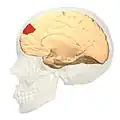

Image

-

Animation.

Animation. -

front view.

front view. -

Lateral view.

Lateral view. -

Medial view.

Medial view.